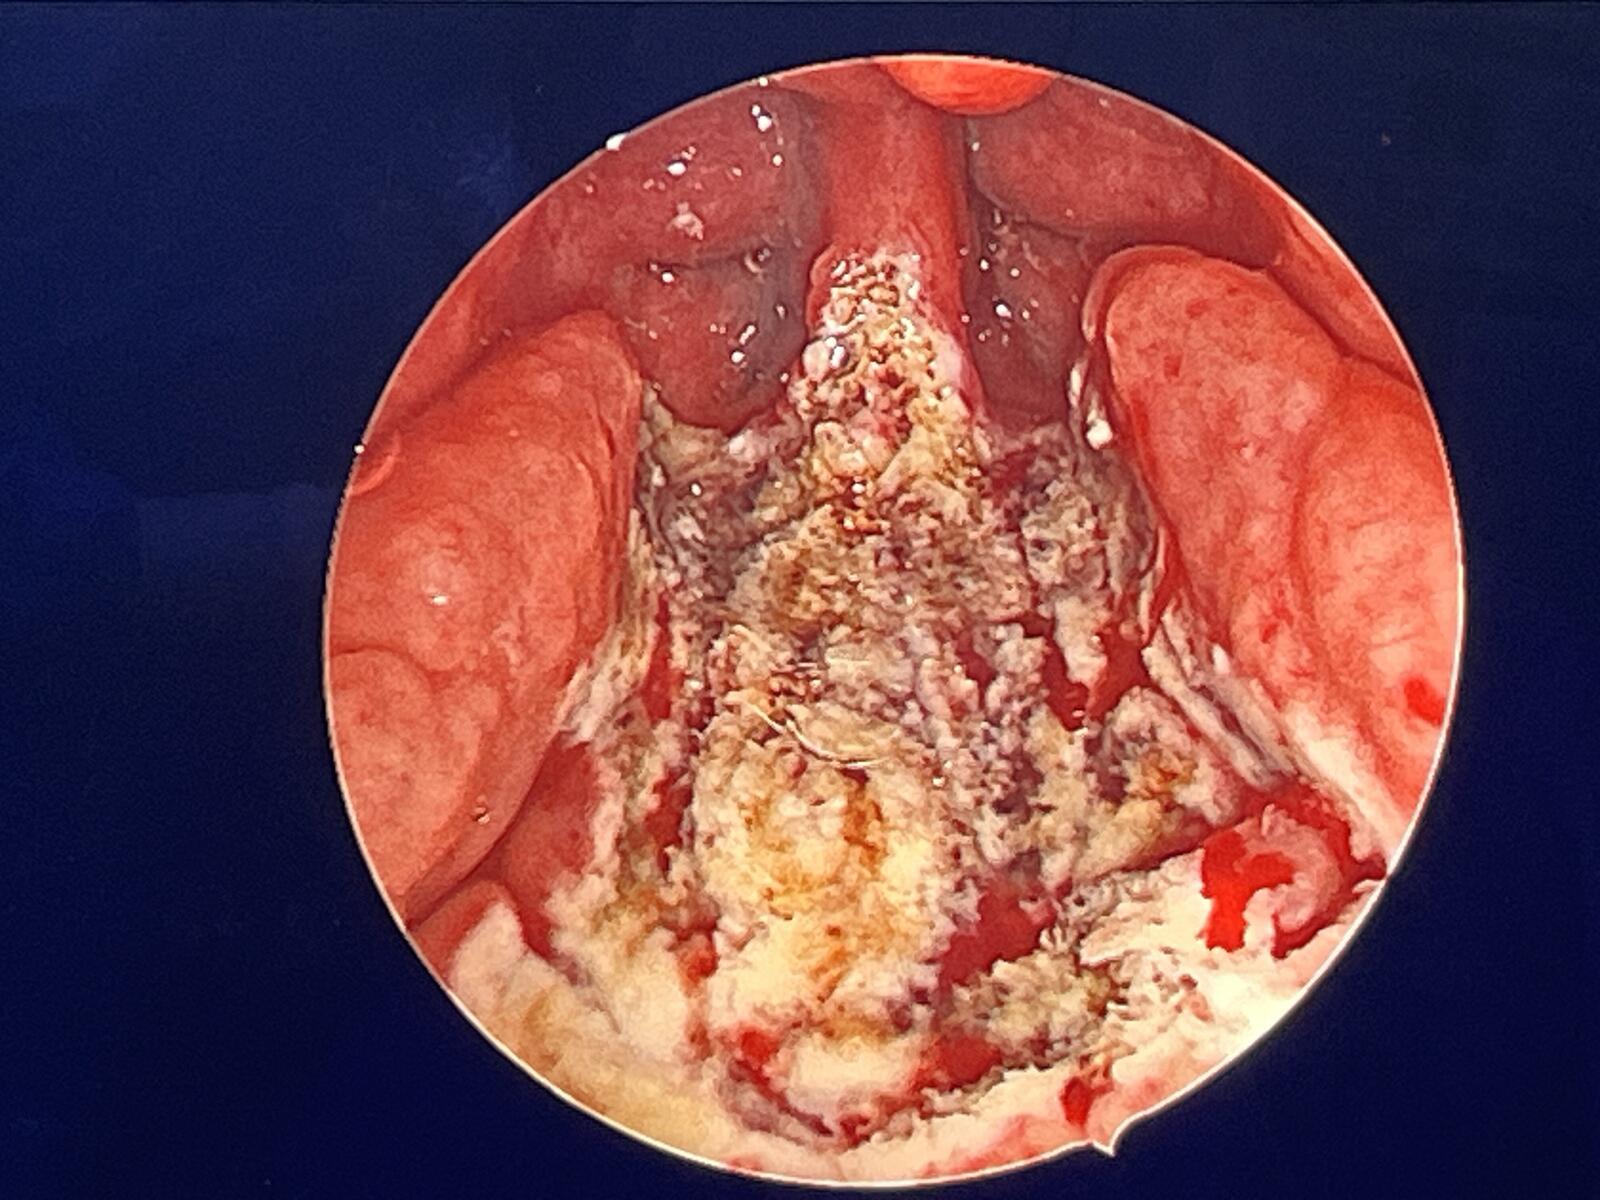

腺样体肥大

母亲手术后的咽腔

处理到位的软腭层面